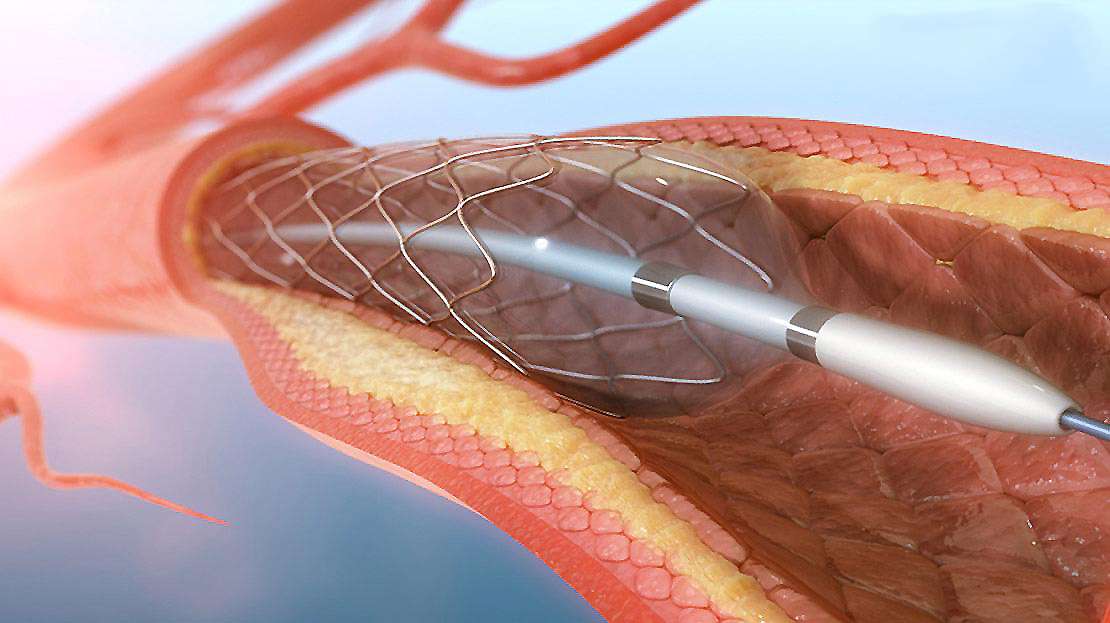

Cerrahi tedavi (Periferik Bypass)

Periferik damar hastalığı tedavisi için uygulanan cerrahi tedavi yöntemleri arasında periferik bypass işlemleri ve endarterektomi bulunmaktadır.Günümüzde minimal invaziv girişimlerle bunlar ayak bileğine kadar olan seviyelerde bile yapılmaktadır. Damar içerisinde tıkanıklığa neden olan lezyonlar, birden fazla darlık içeren damarlar veya uzun segmentli ciddi darlıklar cerrahi tedavi gerektiren durumlardır.

Bypass cerrahisi, vücudunuzdan alınan bir toplardamar veya sentetik bir damar (greft olarak bilinir) ile tıkalı alanın öncesinden sonrasına oluşturulan yan bir yol ile kan akışının sağlanmasıdır. Endarterektomi işleminde ise kol veya bacaklara giden damar içerisinde tıkanıklığa neden olan plak tabakasının çıkarılmasıdır.